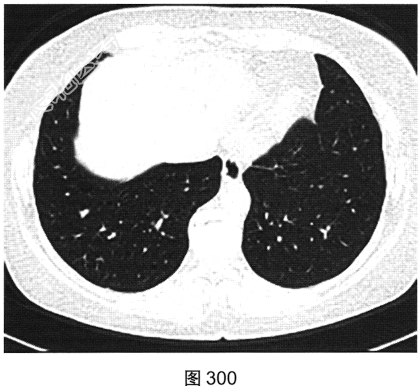

- 多项选择题3.[提示]HRCT图像如图298~图301所示。从患者的HRCT图像中可见哪些阳性征象( )

A、双侧腋窝及纵隔内多发增大淋巴结

B、双肺多发薄壁透亮影

C、小叶间隔增厚

D、右肺多发钙化结节灶

E、双肺多发磨玻璃样密度影

F、支气管扩张

- 多项选择题4.[提示]患者免疫筛查:ANA、RA及干燥综合征相关抗体谱、ACE(一)。根据患者免疫筛查结果, 结合其临床表现和CT影像特征,应优先考虑的诊断是( )

A、肺朗格罕细胞组织细胞增生症

B、支气管扩张

C、淋巴细胞性间质性肺炎

D、肺淋巴管平滑肌瘤病

E、特发性肺间质纤维化

F、肺气肿